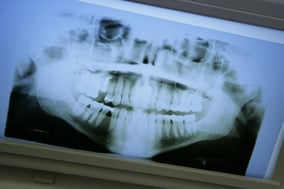

Bei Knochendefekten oder bei Knochenabbau helfen heute moderne Methoden zum Knochenaufbau, so dass Implantate möglich werden.